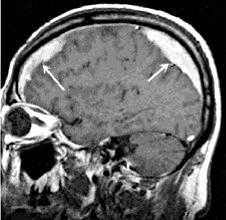

Современные методы нейровизуализации позволяют не только диагностировать внутримозговую гематому, но и выявить причину ее появления. Ведущим диагностическим методом являются:

- КТ головного мозга. Как правило, на томограммах внутримозговая гематома имеет вид очага гомогенной плотности округлой или овальной формы. Если гематома сформировалась в результате ушиба головного мозга, то она обычно имеет неровный контур. С течением времени происходит уменьшение плотности гематомы до изоплотного состояния, при котором ее плотность соответствует плотности мозговой ткани. Для малых гематом этот период составляет 2-3 недели, а для средних — до 5 недель.

- МРТ головного мозга. При уменьшении плотности гематома лучше визуализируется при помощи МРТ, хотя в начальном периоде применение МРТ может привести к ошибочному диагнозу в пользу опухоли с кровоизлиянием. Поэтому, при наличие такой возможности, многие неврологи и нейрохирурги предпочитают использовать в ходе диагностики оба способа нейровизуализации (КТ и МРТ).